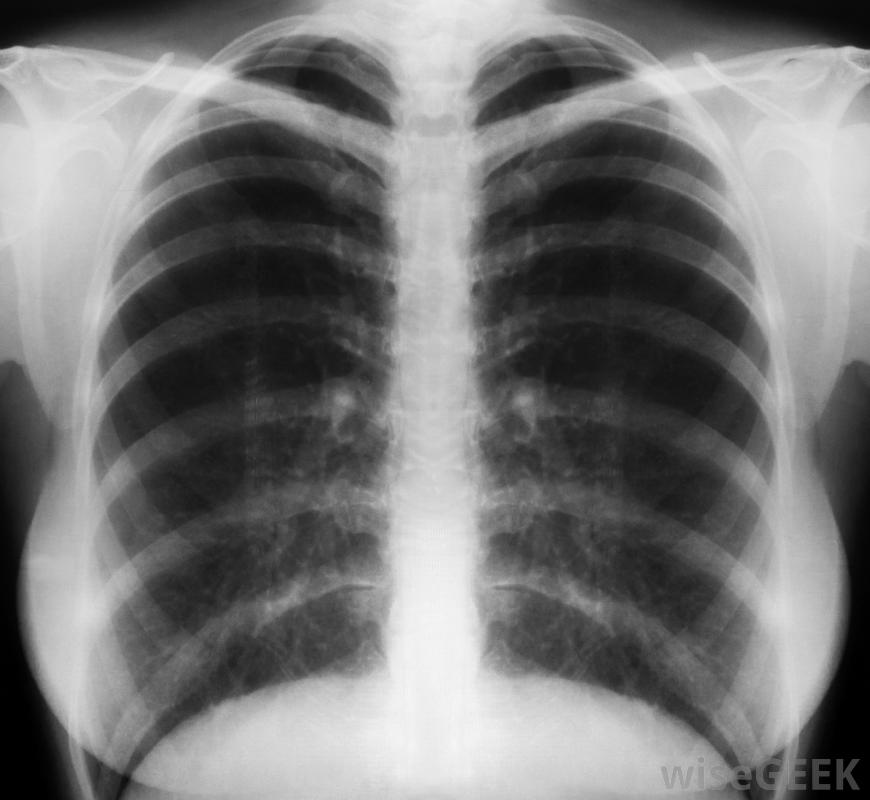

肺囊肿是在一个肺内发现的一种不正常的组织肿块。在大多数情况下,这种肿块是良性的,通常不会引起任何明显的症状。当诊断出肺囊肿时,它通常是由于其他疾病或问题的常规检查结果。偶尔,囊肿可能会恶性的,或癌性的。吸烟、接触环境毒素或既往有癌症病史可能增加囊肿恶性的风险。有时需要对肺囊肿进行活检肺囊肿的出现通常与任何影响肺部的疾病或疾病无关。在大多数情况下,引起这种肿块的确切原因并不清楚通常是良性的,大多数患者没有任何症状,可能完全不知道异常病变,除非诊断测试,如x射线或肺部超声波检查,因为其他原因定期胸部x光检查有助于监测肺囊肿是否有任何变化。在发现肺囊肿后,主管医生可能会要求进行额外的检查,以确保病变没有癌变血液检查通常是为了检查体内癌症时常见的异常情况,为了监测肺囊肿是否有任何变化,如体积增大,可定期进行胸部x光检查在肺活检过程中,可能需要一个小的活检针,在一些病例中被称为肺活检术中的一个小的活检针的大小从囊肿中取出,连同周围的一些组织。这些组织样本被送到外面的实验室做进一步的检查。肺囊肿变得恶性是相对少见的,虽然某些危险因素可能增加结节癌变的几率,但暴露于环境毒素、吸烟和既往癌症史是最常见的危险因素。如果囊肿被确定为良性,则可能不需要治疗,虽然有些医生可能会选择切除病灶以避免其变为恶性,但癌性病变可手术切除或用化疗或放疗治疗。肺癌性肺损伤可以用化疗治疗。